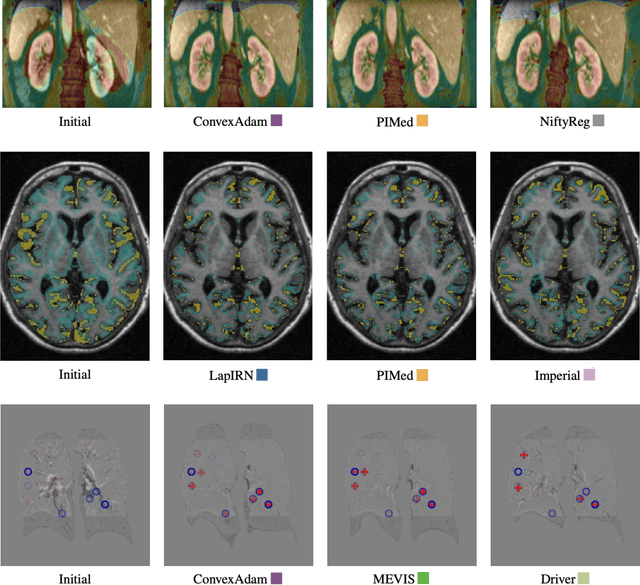

Abstract:Image registration is a fundamental medical image analysis task, and a wide variety of approaches have been proposed. However, only a few studies have comprehensively compared medical image registration approaches on a wide range of clinically relevant tasks, in part because of the lack of availability of such diverse data. This limits the development of registration methods, the adoption of research advances into practice, and a fair benchmark across competing approaches. The Learn2Reg challenge addresses these limitations by providing a multi-task medical image registration benchmark for comprehensive characterisation of deformable registration algorithms. A continuous evaluation will be possible at https://learn2reg.grand-challenge.org. Learn2Reg covers a wide range of anatomies (brain, abdomen, and thorax), modalities (ultrasound, CT, MR), availability of annotations, as well as intra- and inter-patient registration evaluation. We established an easily accessible framework for training and validation of 3D registration methods, which enabled the compilation of results of over 65 individual method submissions from more than 20 unique teams. We used a complementary set of metrics, including robustness, accuracy, plausibility, and runtime, enabling unique insight into the current state-of-the-art of medical image registration. This paper describes datasets, tasks, evaluation methods and results of the challenge, and the results of further analysis of transferability to new datasets, the importance of label supervision, and resulting bias.